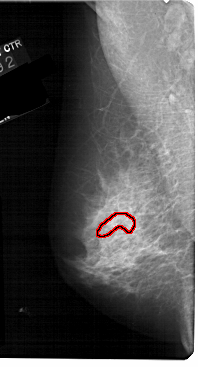

A_1130_1.LEFT_CC

LEFT_CC LINES 5071 PIXELS_PER_LINE 2311 BITS_PER_PIXEL 12 RESOLUTION 43.5 OVERLAY

FILE: A_1130_1.LEFT_CC.OVERLAY

TOTAL_ABNORMALITIES 1

ABNORMALITY 1

LESION_TYPE CALCIFICATION TYPE FINE_LINEAR_BRANCHING DISTRIBUTION SEGMENTAL

ASSESSMENT 5

SUBTLETY 4

PATHOLOGY MALIGNANT

TOTAL_OUTLINES 1

BOUNDARY